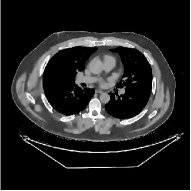

This paper was inspired by a simple observation related to our recent study [34]: for the penalized weighted-least squares (PWLS) reconstruction method using prior with a learned ST (PWLS-ST-) [34], the sparsification error histograms match a Laplace distribution over the iterations; see Fig. 1. The question then arises, “Does the learned prior experience model mismatch in testing stage?” To answer this question, we aim to investigate learned STs for regularization. This paper

The term denotes a -based sparsification error [3, 4, 5]. We expect to be more robust to sparsity model mismatch than the -based sparsification error used in [34, 36]. Fig. 1 shows histograms of sparsification error at different outer iterations of the PWLS-ST- method. Over the iterations, the sparsification error histograms appear more like a Laplace distribution than a Gaussian distribution. This observation suggests that the proposed prior model is more suitable than the prior model for PWLS-ST-based reconstruction. Section III-B1 shows that the proposed -based sparsification error term, , improves the accuracy of reconstruction compared to the prior model in [34, 36].